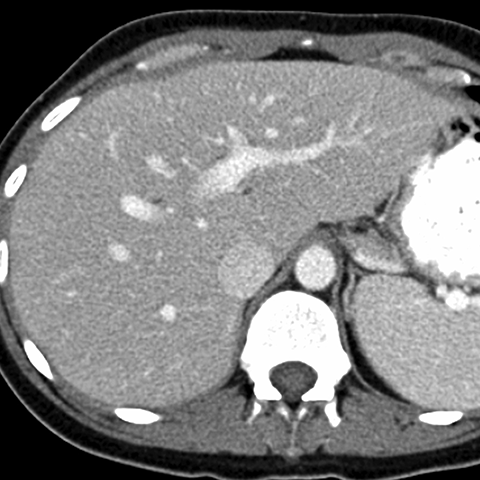

Normal Liver, CT ( axial ) [3 of 9]